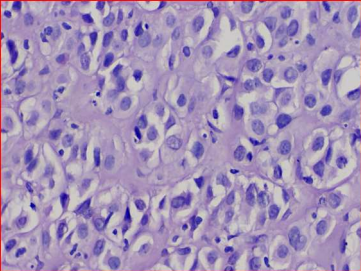

Figure 7: Sheets of malignant tumor cells separated by fibrous connective tissue septae and eosinophilic areas resembling tumor osteoid surrounded by malignant osteoblasts.

Figure 8: Clear cells- round to oval in shape with vesicular nuclei and clear cytoplasm with some binucleation resembling chondroid like areas

A 14-year old female patient reported with an ulcerative lesion of the right posterior region of the jaw associated with mobility of teeth 46 and 47 since 1 month (Fig 5). The patient was apparently normal 1 month back after which the lesion was noted. CBCT shows a solitary large ill-defined expansile osteolytic lesion of mixed density in the region extending from 46 to the right body and ramus of the mandible (Fig 6). A provisional diagnosis of aggressive neoplastic lesion such as odontogenic myxoma and osteosarcoma was considered. Incisional biopsy was performed and the H and E stained sections shows sheets of malignant tumor cells separated by fibrous connective tissue septae. The malignant cells displayed atypical features such as cellular and nuclear pleomorphism, nuclear hyperchromatism and few bizarre shaped cells. Presence of eosinophilic areas resembling tumor osteoid surrounded by malignant osteoblasts was evident. In addition, the sections also showed a sub-population of clear cells which were round to oval in shape with vesicular nuclei and clear cytoplasm with some binucleation resembling chondroid like areas (Fig 7 & 8). Special staining for PAS and mucicarmine to rule out clear cell odontogenic carcinoma and intra-osseous mucoepidermoid carcinoma was negative. Based on these findings the final diagnosis was chondroblastic variant of osteosarcoma. Hemimandibulectomy was performed and the final diagnosis of the excised specimen was high grade osteosarcoma. Six month follow-up was uneventful.